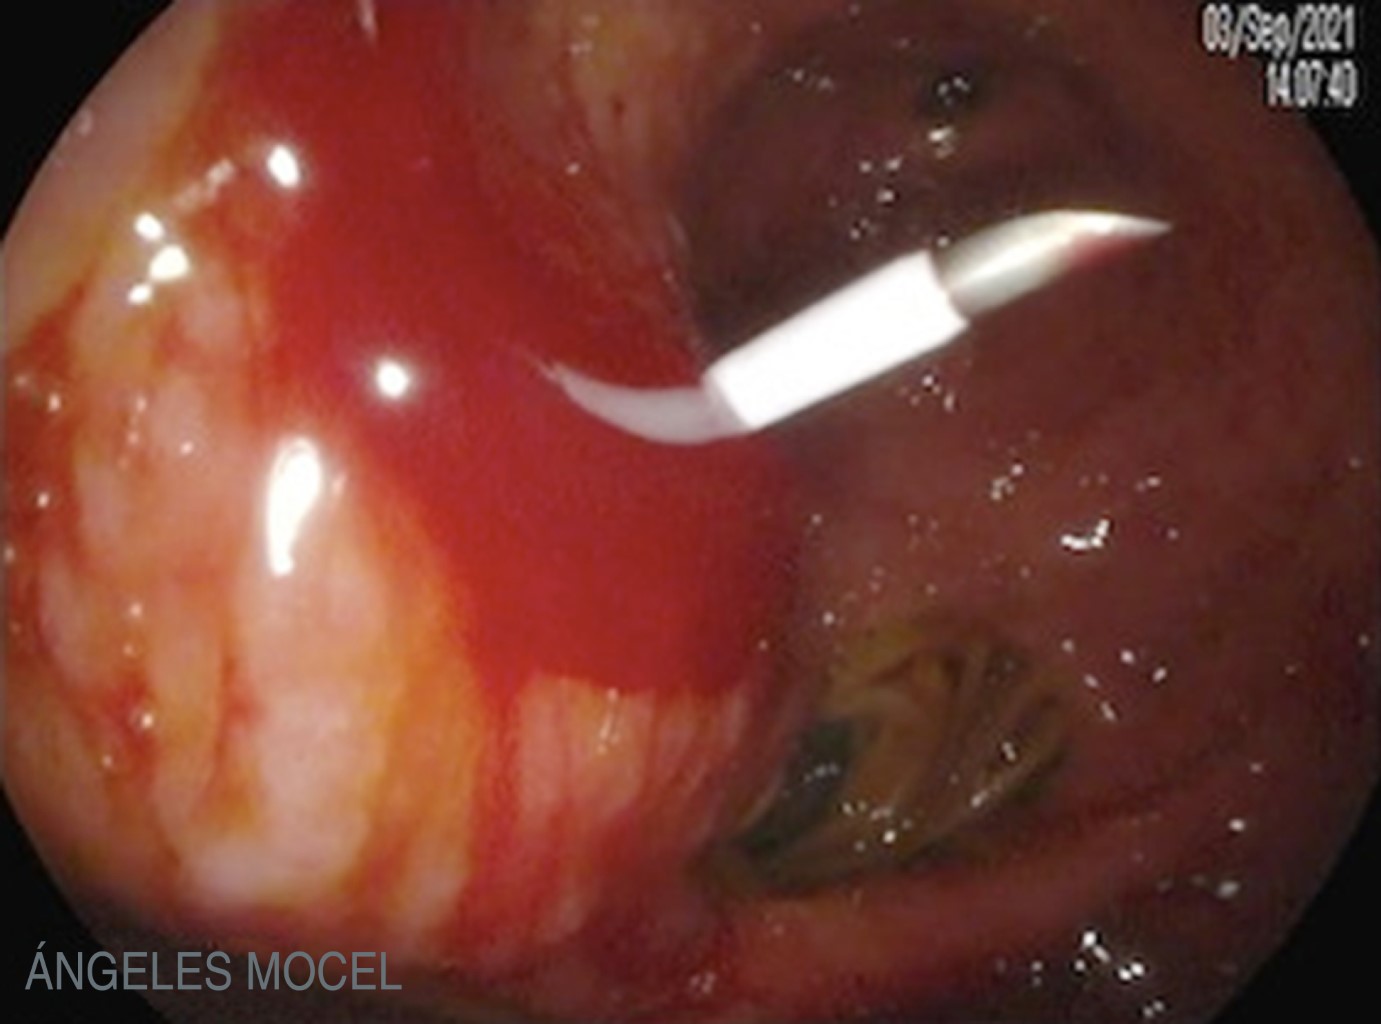

Figure 4